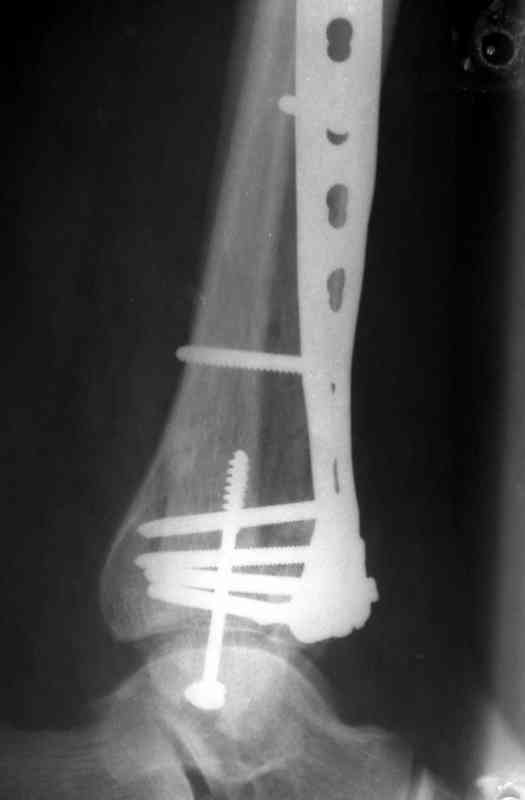

Послала ещё два снимка, если не пройдут, пошлю ещё. Дрягин. Если есть вопросы, готов ответить.

Посылаю результат лечения предыдущего больного через год.

Кстати, при переломах переднего края по классификации АО В-3 при переломах пилона пластина укладывается по передней поверхности. Она достаточно тонкая и эластичная, не надо этого бояться. Посылаю три снимка.